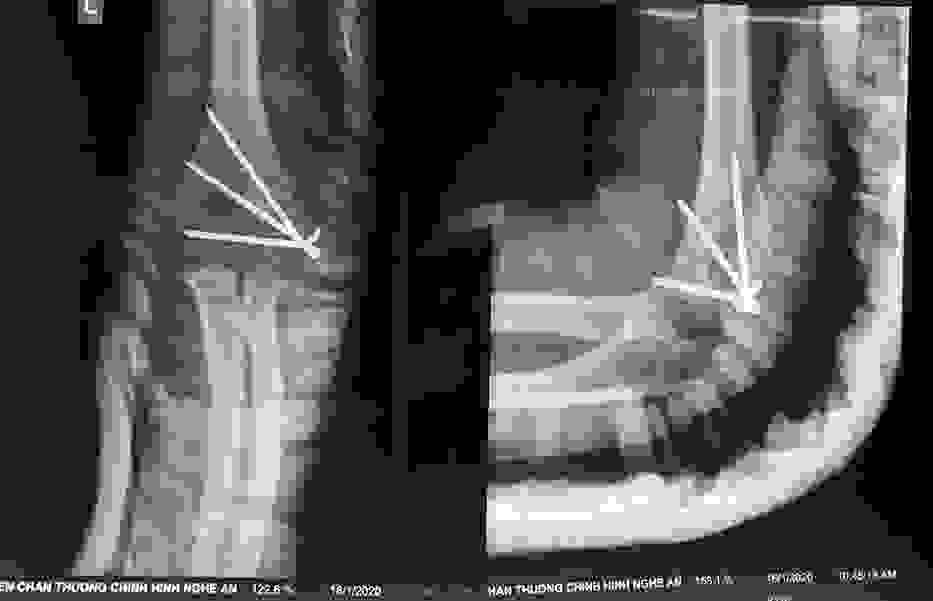

Phẫu thuật thành công ca bệnh hiếm gặp...khớp giả bẩm sinh xương chày

26/06/2019 17:00

Đã xem: 3366

Bệnh viện Chấn thương- Chỉnh hình Nghệ An, vừa phẫu thuật thành công cho bệnh nhi khớp giả bẩm sinh xương chày